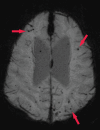

Neurodegenerative diseases are a devastating group of disorders that can be difficult to accurately diagnose. Although these disorders are difficult to manage owing to relatively limited treatment options, an early and correct diagnosis can help with managing symptoms and coping with the later stages of these disease processes. Both anatomic structural imaging and physiologic molecular imaging have evolved to a state in which these neurodegenerative processes can be identified relatively early with high accuracy. To determine the underlying disease, the radiologist should understand the different distributions and pathophysiologic processes involved. High-spatial-resolution MRI allows detection of subtle morphologic changes, as well as potential complications and alternate diagnoses, while molecular imaging allows visualization of altered function or abnormal increased or decreased concentration of disease-specific markers. These methodologies are complementary. Appropriate workup and interpretation of diagnostic studies require an integrated, multimodality, multidisciplinary approach. This article reviews the protocols and findings at MRI and nuclear medicine imaging, including with the use of flurodeoxyglucose, amyloid tracers, and dopaminergic transporter imaging (ioflupane). The pathophysiology of some of the major neurodegenerative processes and their clinical presentations are also reviewed; this information is critical to understand how these imaging modalities work, and it aids in the integration of clinical data to help synthesize a final diagnosis. Radiologists and nuclear medicine physicians aiming to include the evaluation of neurodegenerative diseases in their practice should be aware of and familiar with the multiple imaging modalities available and how using these modalities is essential in the multidisciplinary management of patients with neurodegenerative diseases.©RSNA, 2020.